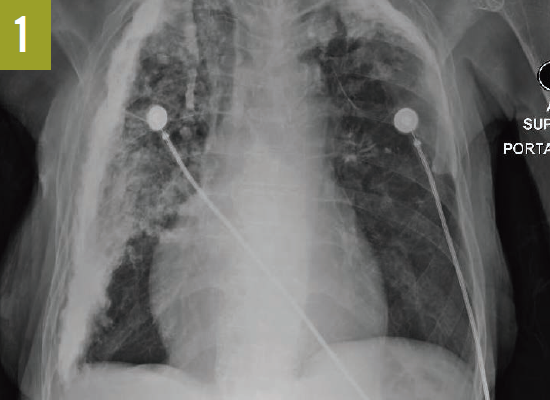

Upon admission, a chest radiograph revealed hyperlucency of the right hemithorax with a right basilar infiltrate (Figure 1). Computed tomography (CT) of the chest showed extensive unilateral bullous emphysema involving the entire right lung from apex to base (Figure 2). The emphysema was confined to one side and was so severe and voluminous that the mediastinum was pushed far away from its midline alignment with the sternum into the left hemithorax, resulting in compression and atelectasis of the left lung. There was also a right-sided pneumonia superimposed on the background of emphysema.

Figure 1. A chest radiograph showed hyperlucency of the right hemithorax and a right basilar infiltrate.

Figure 2. A CT scan of the chest at the level of the carina showed severe and voluminous bullous emphysema of the right lung; the mediastinum is pushed far away from its midline alignment with the sternum into the left hemithorax, and a right basal pneumonia is present.